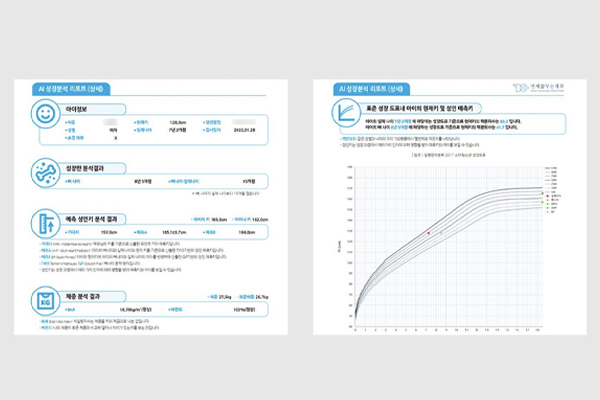

이지민 대표원장이 공동 연구한 AI 기반 성장판 분석 논문의 학술적 근거를 바탕으로,

정밀 성장판 검사 프로그램을 통해 성장기 아동의 성장 페이스를 정확히 예측하고

최적의 교정 시기와 치료 계획을 설계합니다.

소아청소년기의 정상적인 성장 여부 판단을 위해

손뼈 엑스레이를 분석하여

높은 정확도의 골연령 판독 결과를 제시합니다.

엑스레이 판독 결과와 키와 몸무게 등의

환자 정보를 함께 평가하여 환자의 예상 신장을 비롯한

유용한 성장 정보를 담은 리포트를 제공합니다.